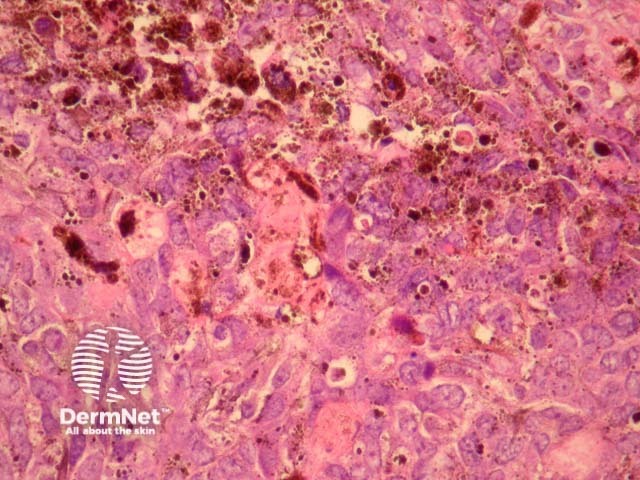

Sections through melanocytic matricoma show a well-circumscribed dermal tumour which may encroach and erode the overlying epidermis (figure 1). There is heavy melanin deposition. The tumour is made up of basaloid cells with some nuclear pleomorphism and conspicuous mitotic activity. Intermixed with these epithelial cells are a population of dendritic melanocytes (figures 1-4). There is focal “ghost cell” keratinisation (figures 5, 6).

Figure 2